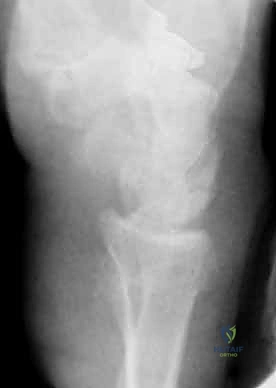

كسر عنق الفخذ: العلاج الحديث بالمسامير المجوفة عبر الجلد مع الأستاذ الدكتور محمد هطيف في صنعاء

اكتشف أحدث طرق علاج كسر عنق الفخذ بالمسامير المجوفة عبر الجلد مع أ.د محمد هطيف، استشاري جراحة العظام والمفاصل في صنعاء. تخلص من الألم واستع…